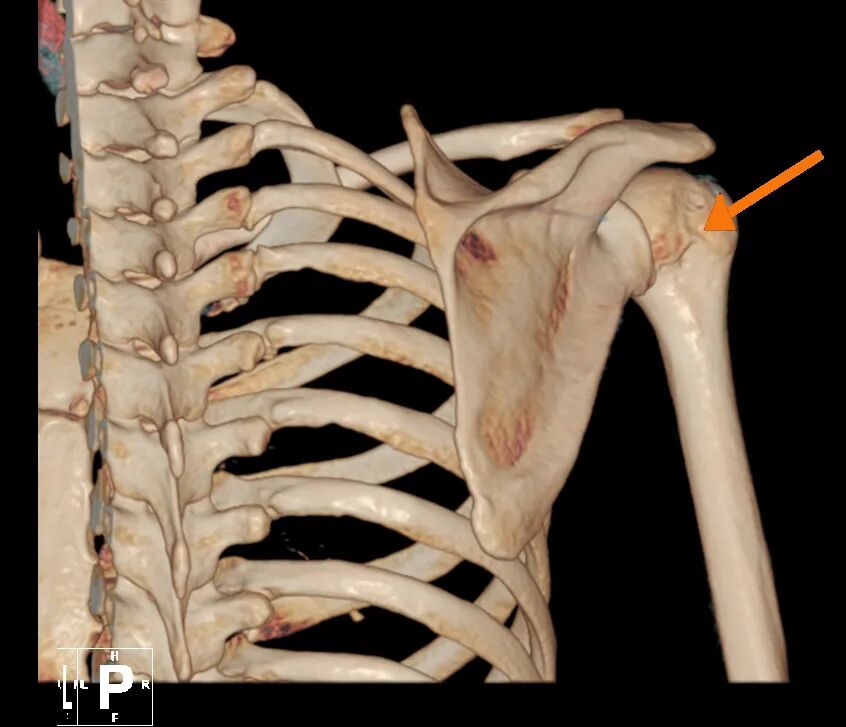

肩关节前盂唇撕裂

肱骨头骨缺损

针对林女士的病情,叶庭均与安亭医院骨科团队制定了关节镜微创手术方案。该手术仅需在肩部开数个不足1厘米的小切口,通过内置摄像头与精密器械精准修复受损部位,具有创伤小、恢复快的优势。手术中,医生发现其肩关节前盂唇存在明显撕裂,并伴有肱骨头骨缺损,随即进行了盂唇修复与关节囊固定术,重建了肩关节稳定性。术后,林女士在骨科团队指导下逐步进行康复训练,肩关节功能恢复顺利,目前已重返日常生活。